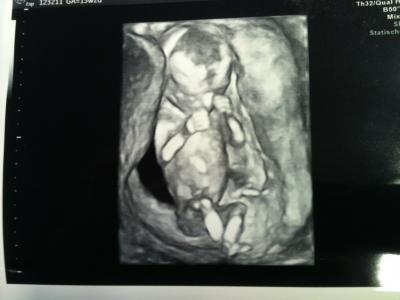

Hallo Ihr Lieben, ich hatte diese Woche bereits zweimal das Vergnügen unseren Krümel zu sehen. Am Dienstag waren wir zum Ersttrimesterscreening in einer Spezialpraxis. Nach mehr als 2,5 h Wartezeit durften wir dann aber 45 min lang Baby-TV gucken. Ich war die ganze Zeit nur still fasziniert aber mein Schatz hat die Ärztin mit Fragen gelöchert. Der Ultraschall hat ergeben, dass alles in bester Ordnung ist. Alles ist dran und drin und da wo es hin soll. Ich war vorher ziemlich aufgeregt und hinterher richtig happy. SSL ist inzwischen 7,2 cm und wir haben auch schöne Bilder bekommen. Zwei hänge ich mal mit ran. Heute morgen war ich dann noch einmal kurz bei meiner FÄ weil diese von mir auch den Bericht haben wollte und da hat sie dann noch einmal schnell US gemacht. Nächster Termin ist dann der 01.02. Ich wünsch euch noch einen schönen Tag, Katja

Bild zu Mein FA-Bericht - Forum für Juli - Mamis

Ja, vor allem ist unser Krümel da ja auch für Laien gut erkennbar, so dass sogar meine Tochter meinte, sieht schon aus wie ein Baby und nicht mehr wie ein Alien.